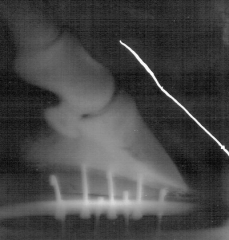

Les rayons X du sabot démontrent que certains chevaux qui sont très sensibles aux aplombs irréguliers ou qui souffrent d'une boiterie partielle, ont une troisième phalange de faible densité. Les rebords de l'os sont irréguliers en raison d'une nouvelle formation osseuse.

Ce phénomène est plus fréquent dans les talons. Des os affectés peuvent provoquer une légère boiterie chronique dans un ou dans plusieurs sabots. Cette affection est causée par des chocs répétés. Un nouvel os est alors formé à la suite d'une inflammation de la troisième phalange (ostéite). Une pression sur les couches sensibles de la sole est alors effectuée. Des chevaux de plus grande taille qui ont des sabots plats (dont les soles ne sont pas concaves), sont plus sensibles à cette affection. Le diagnostic n'est pas toujours précis.

C'est ainsi que les animaux qui présentent les mêmes formations à travers les rayons X et qui ne manifestent pas de signes de boiterie, sont souvent confrontés au même problème. Pour confirmer le diagnostic, on est souvent obligé de procéder à un blocage nerveux sur le sabot.